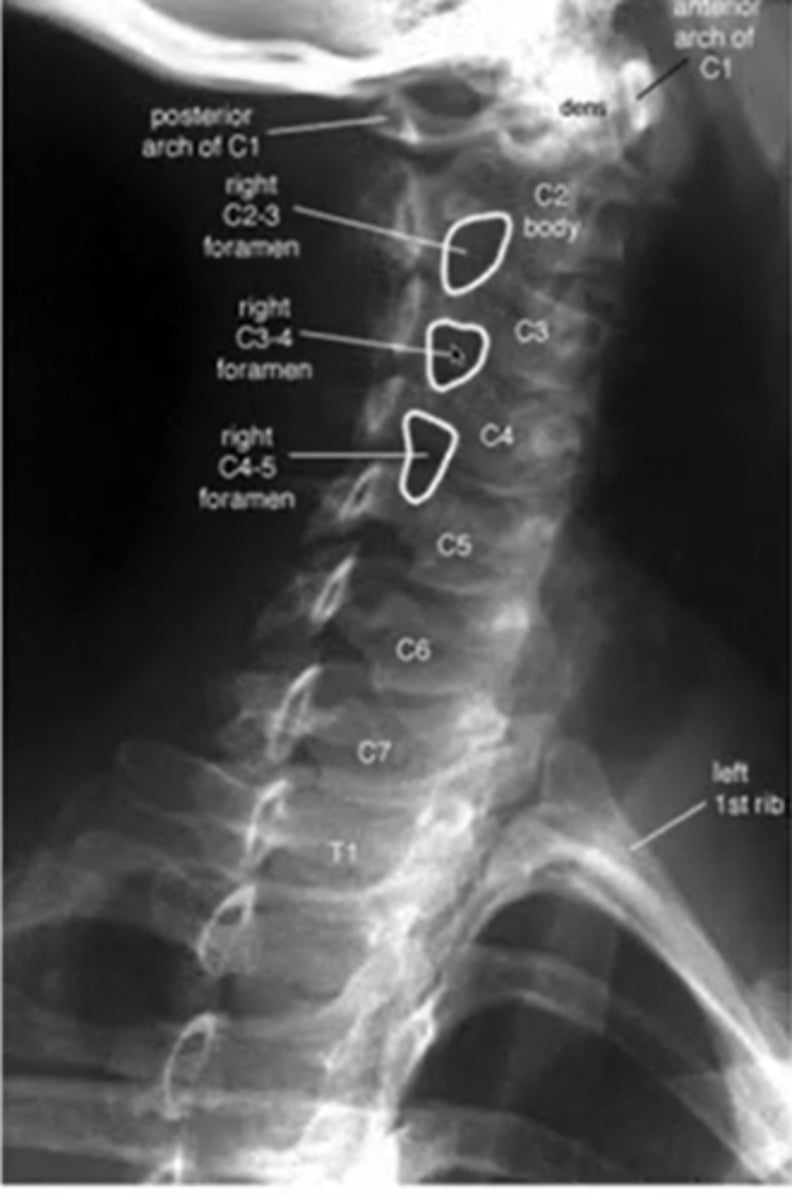

after a trumatic event to the C/S what image will you expect them to take

AP open mouth view

what does a normal AP x-ray of C1-2 look like

what does a left oblique cs image look like

(it says right but its really left)